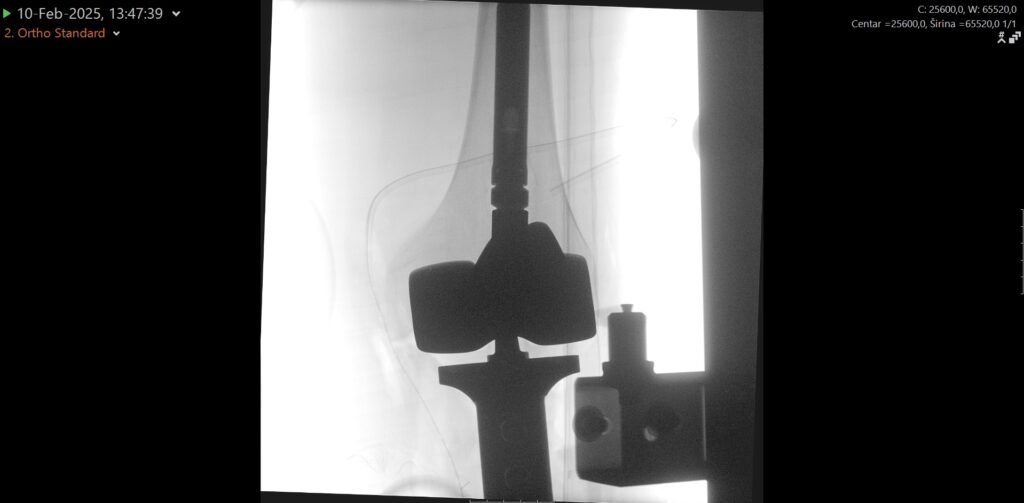

No to više nije potrebno jer je zahvat uspješno obavljen u splitskoj bolnici, i to baš mladom Splićaninu, koji se dobro oporavlja. Tijekom zahvata u potpunosti mu je odstranjen koljenski zglob te gornjih 17 cm goljenične kosti koji su zamijenjeni posebnom tumorskom protezom i nadomjestkom – implantatom za odstranjenu kost. Potom je nastali defekt primarno zatvoren i pokriven kožno-mišićnim režnjem.

Zahvat je obavio tim Zavoda za ortopediju i traumatologiju, uz vodstvo posebnog gosta dr. Marka Bergovca, predstojnika Klinike za ortopediju i traumatologiju Klinike Diakonissen iz Schladminga i vodećeg stručnjaka u području rekonstruktivne i tumorske ortopedske kirurgije. Djelatnici Zavoda za ortopediju i traumatologiju izrazito su zadovoljni što su im pacijent i njegova obitelj poklonili povjerenje kako bi se ovaj složen i zahtjevan zahvat obavio upravo u KBC Split umjesto odlaska u neku od inozemnih klinika.